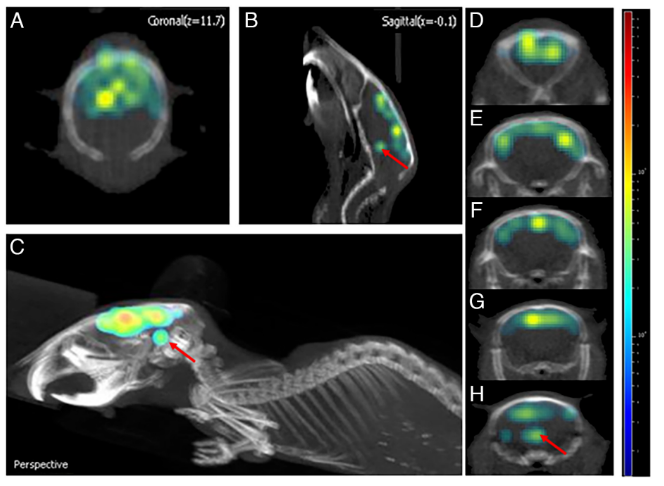

在小鼠的3D腦成像研究中,作者發(fā)現(xiàn)信號可達(dá)小鼠腦部深層0.5 cm處(圖4)。并且,對比野生型和AD小鼠不同位置的3D腦成像信號強(qiáng)度均有不同,差別可達(dá)2.72倍,相較于二維腦成像的信號差別(1.8倍)有所增加。所以,該方法不僅可以區(qū)分健康和AD小鼠,同時也提高了定量分析結(jié)果(圖5)。

圖4. ADLumin-5探針的三維腦成像。圖片來源:PNAS